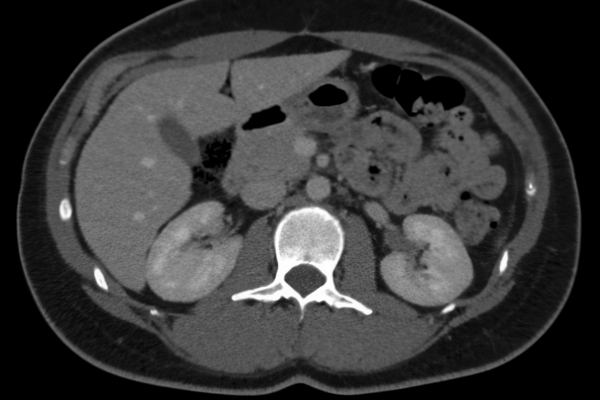

CT Untersuchung Bild